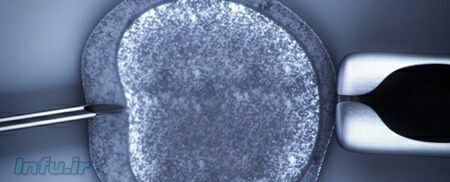

دانشمندان برای اولینبار توانستند با موفقیت در فضای آزمایشگاهی از اولین مراحل باروری انسان تخمک پرورش دهند، موفقیتی که میتواند به روشن شدن روند شکلگیری تخمک و کمک به درمان ناباروری کمک کند.

براساس گزارش گاردین، محققان دانشگاه ادینبورگ برای انجام اینکار بافت تخمدان ۱۰ داوطلب ۲۰ تا ۴۰ ساله را برداشته و با استفاده از مواد مغذی متفاوت تخمکها را تا مرحله پیش از باروری پرورش دادند. در این فرایند ۴۸ تخمک به مرحله نهایی رسیده و ۹ تخمک به بلوغ کامل دست یافت.

سالها طول کشیده تا دانشمندان بتوانند تخمک را خارج از رحم پرورش بدهند. پرورش تخمک در خارج از تخمدان کار آسانی نیست و به تنظیم دقیق میزان اکسیژن، هورمون و پروتئین نیاز است. همچنین دانشمندان کنجکاوند بدانند چرا تخمکهایی که پرورش دادهاند با سرعتی بالاتر از درون بدن رشد میکنند.